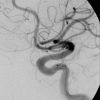

A 35-year-old man's vision had progressively deteriorated over a 3-month period. His left visual acuity was 5/20. Enhanced orbital computed tomographic (CT) scans revealed a fusiform dilatation of the ophthalmic artery in the left optic canal. Cerebral Angiography revealed a fusiform aneurysm on the left ophthalmic artery in the optic canal, measuring 6.2 x 4.6 mm in size. Four days after admission, visual acuity dropped to hand-motion. Endovascular treatment was chosen and a microcatheter was guided into the proximal segment of the ophthalmic artery. Using 4 detachable coils, parent artery occlusion was done. Three months after the intervention, the visual acuity in his left eye improved to 20/20. Dramatic recovery of visual acuity is exceptional with an ophthalmic artery trunk aneurysm. When an occlusion of the proximal ophthalmic artery is the only treatment option in such a situation, the endovascular occlusion of the proximal ophthalmic artery is quite feasible in the sense that it does not require any optic nerve manipulation.